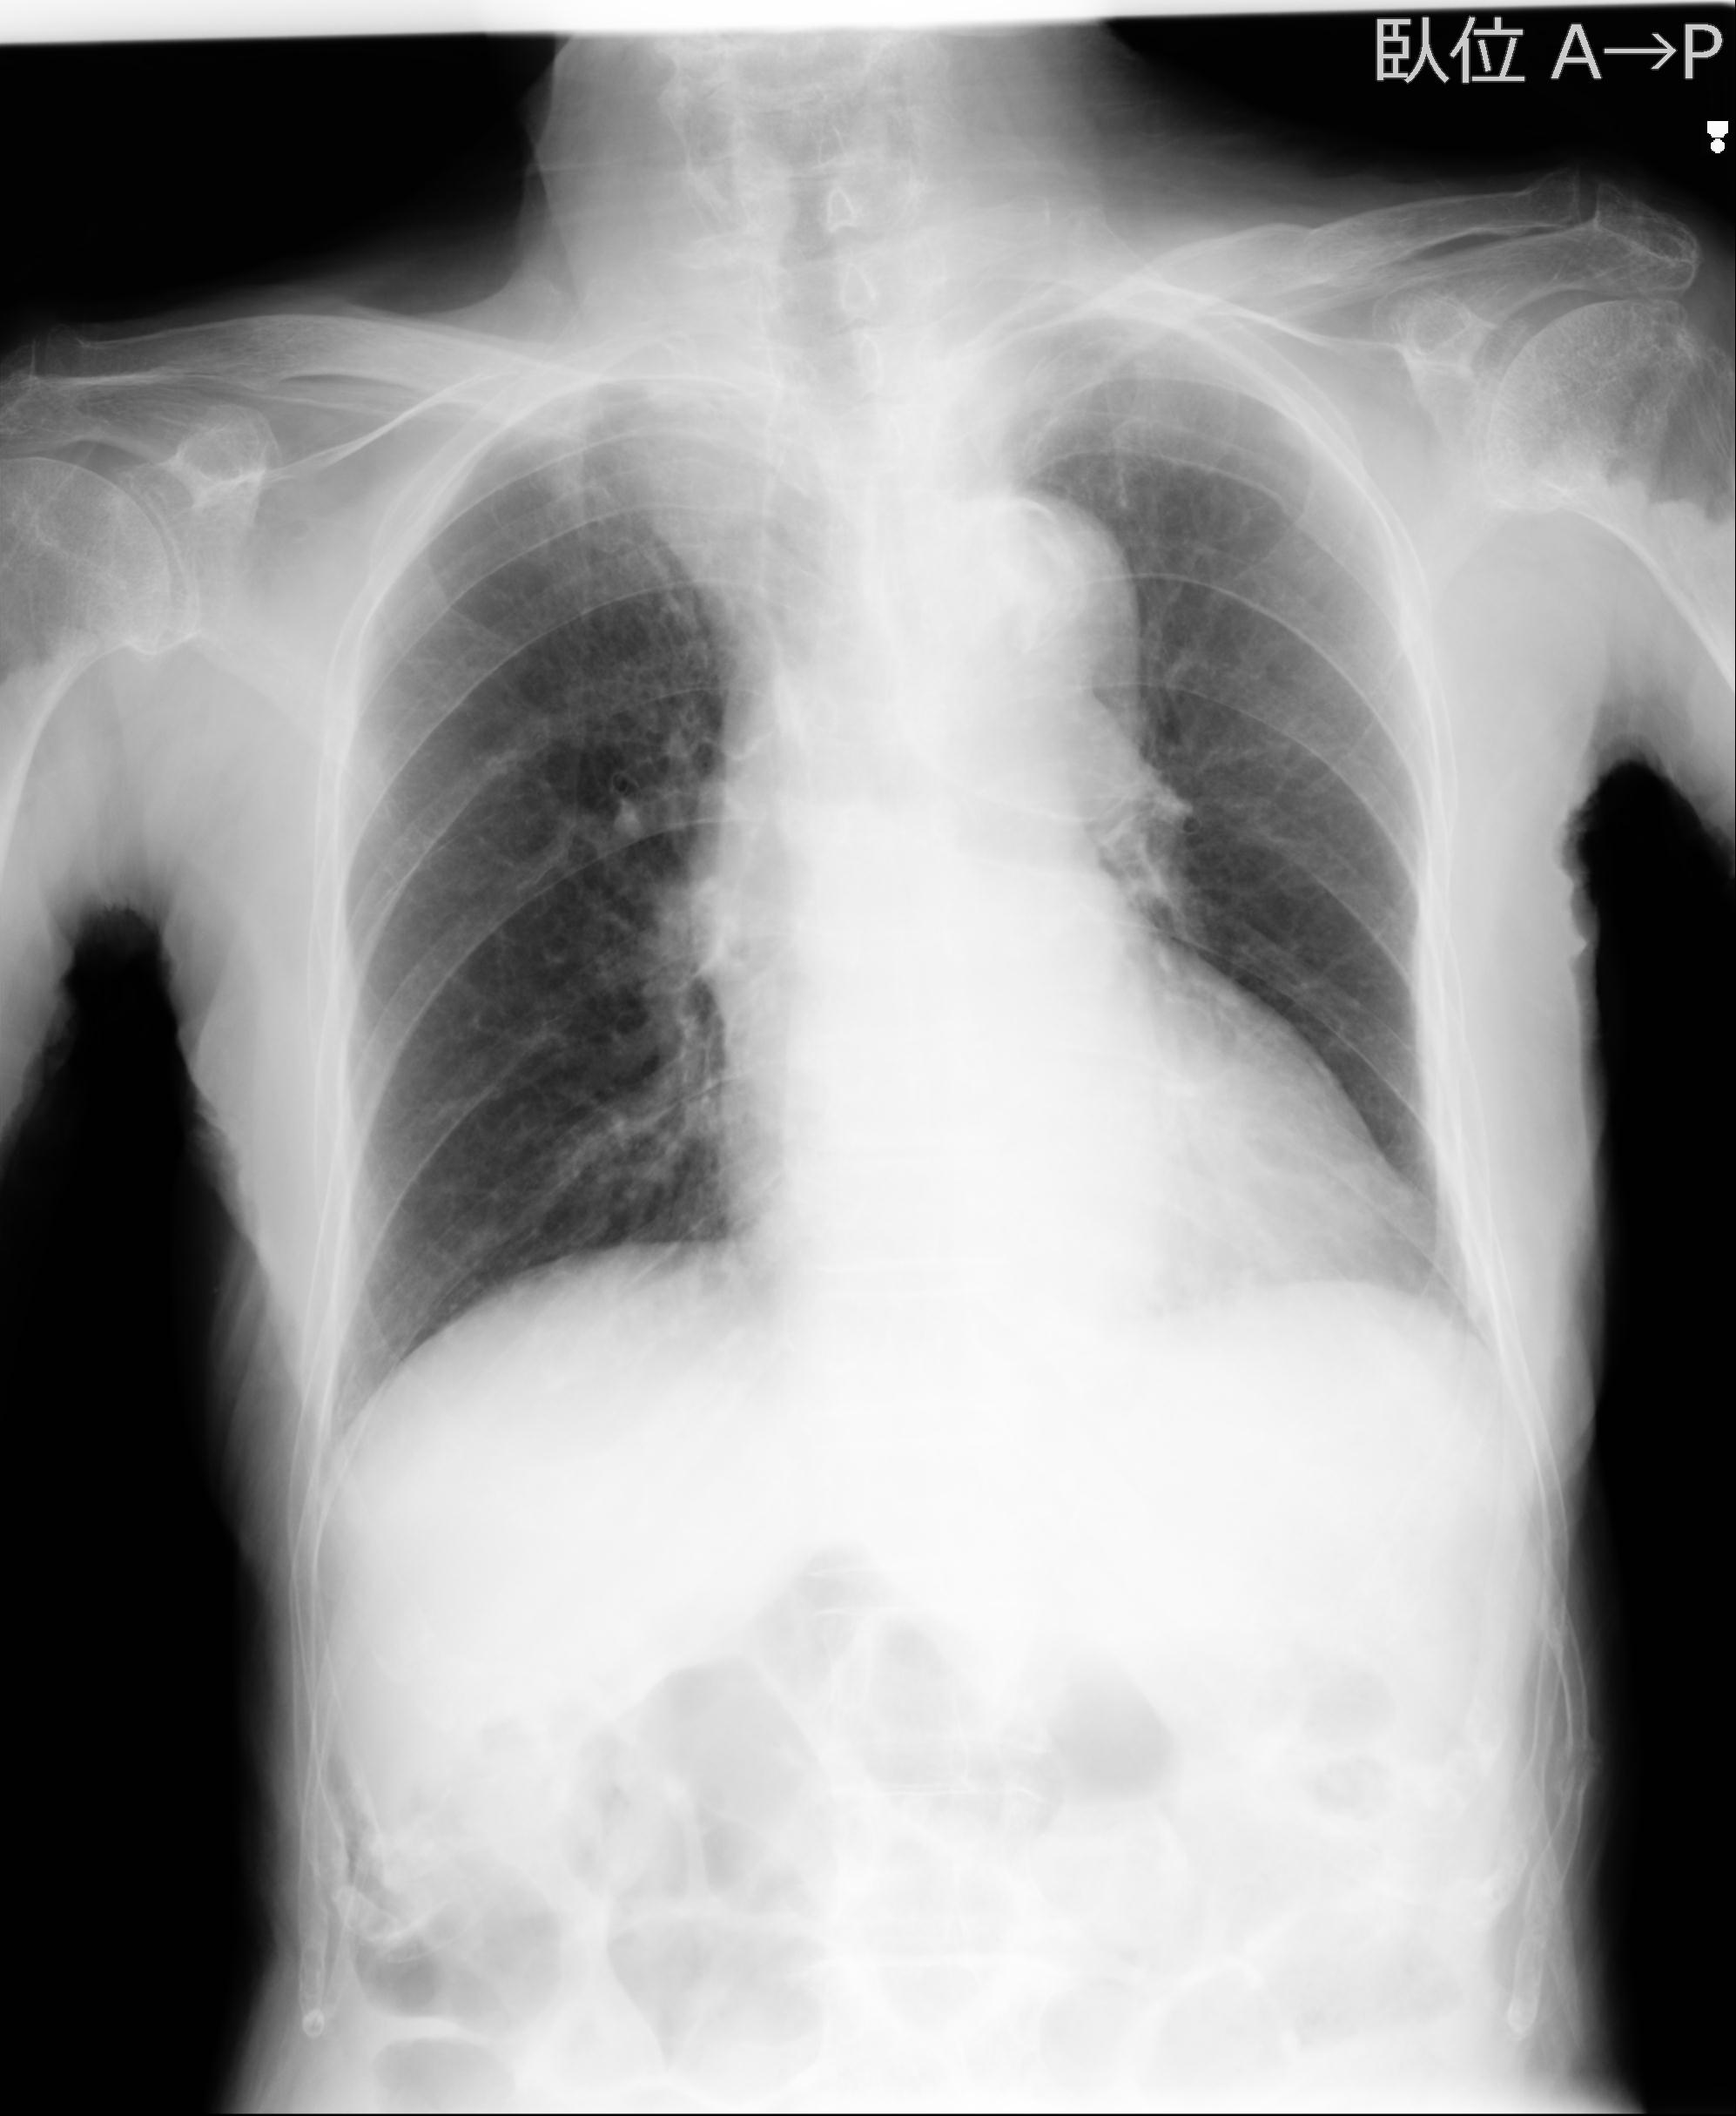

110214 12/20 肩 2R 12/21 肩 4R 72歳女性 左上腕外科頚プレート